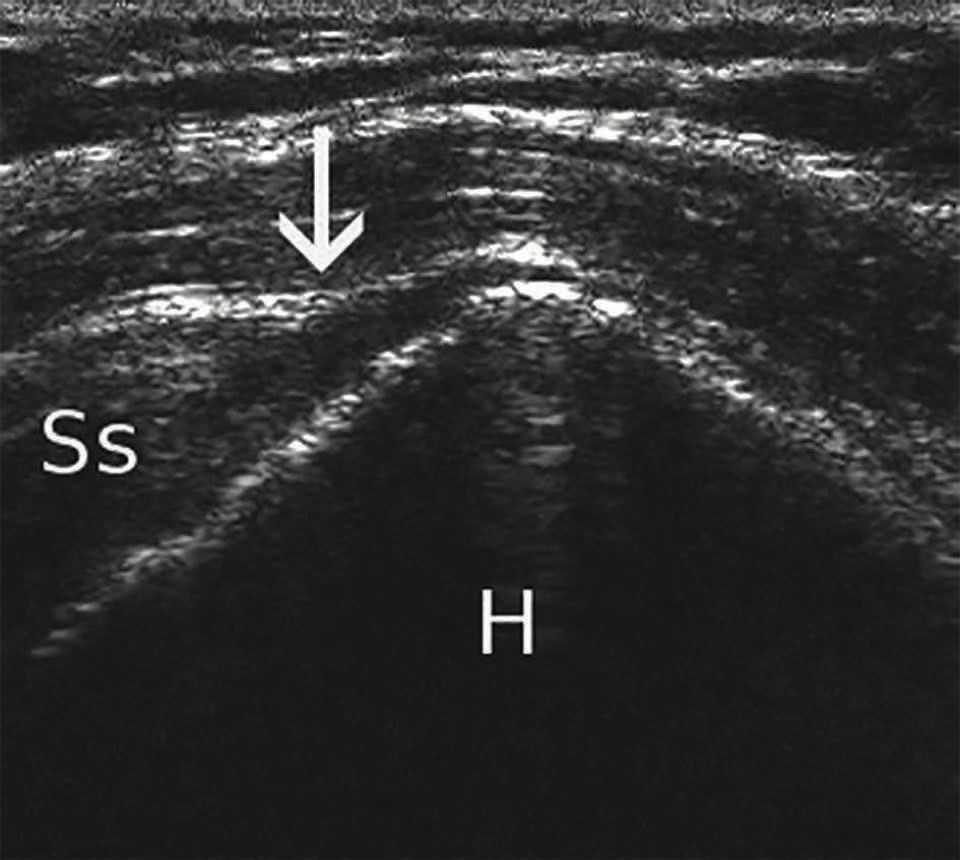

Technique Ligamentoplastie du LCA aux ischio-jambiers pédiculés et conservation du reliquat ligamentaire , Matthieu Ehlinger Hôpital de Hautepierre, Strasbourg, France 🖂 matthieu.ehlinger@chru-strasbourg.fr , François Bonnomet Hôpital de Hautepierre, Strasbourg, France , Olivier Siegrist Hôpital de Hautepierre, CHU Strasbourg, 67098 Strasbourg, France , Beat Kaspar Moor Hôpital de Martigny, Martigny, Suisse , Philippe Adam Hôpitaux Universitaires de Strasbourg, Strasbourg, France , Sébastien Lustig Hôpital de la Croix-Rousse, Centre Albert Trillat, Lyon, France N°258 Cahier 2 - Novembre 2016 ● 8 min de lecture